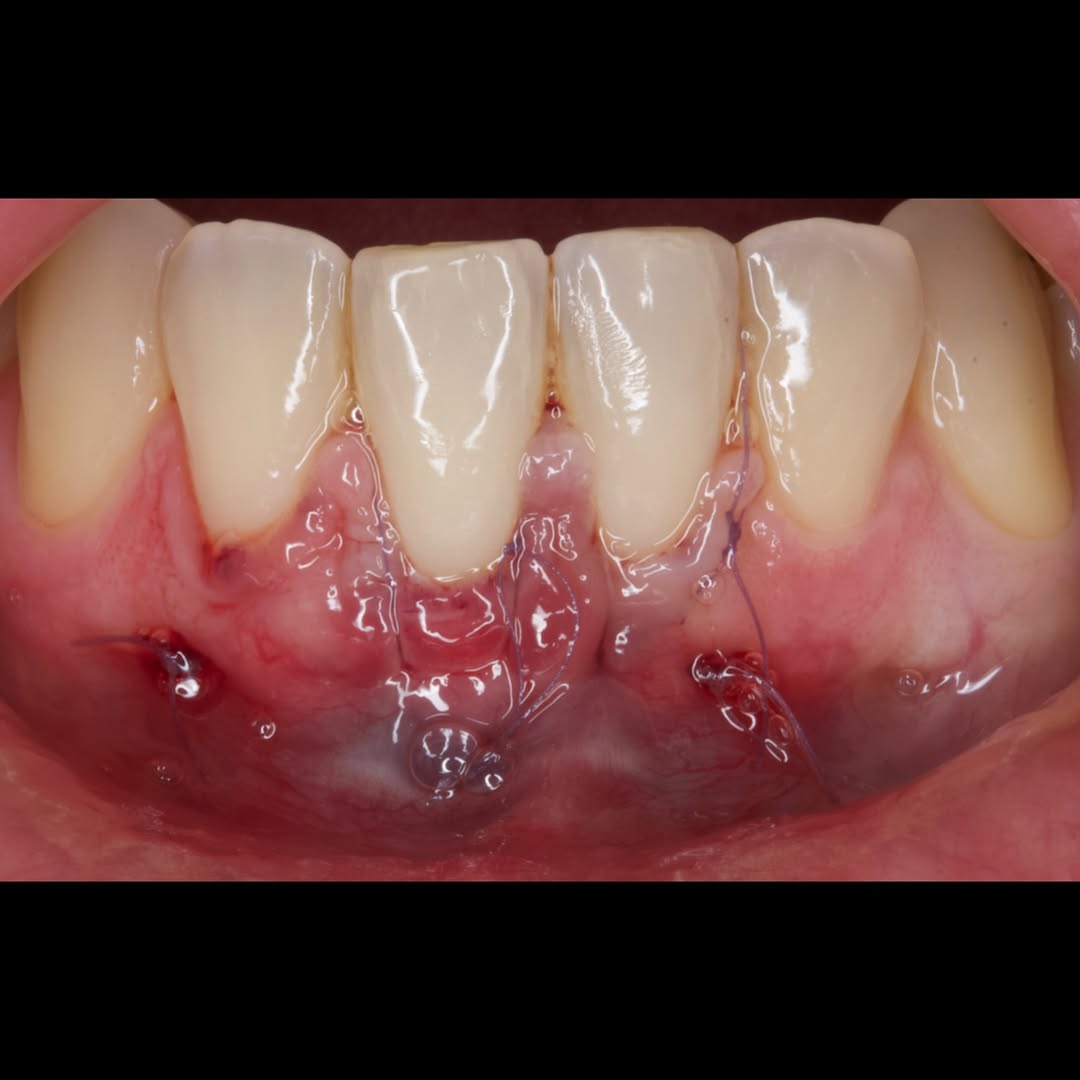

Durante una mañana, asistirás a una Cirugía Mucogingival de recubrimiento radicular de una recesión unitaria en 31 con frenillo asociado. Gracias al uso del microscopio y a la proyección en tiempo real en pantalla, verás exactamente lo mismo que veo yo durante la cirugía, sin tener que estar